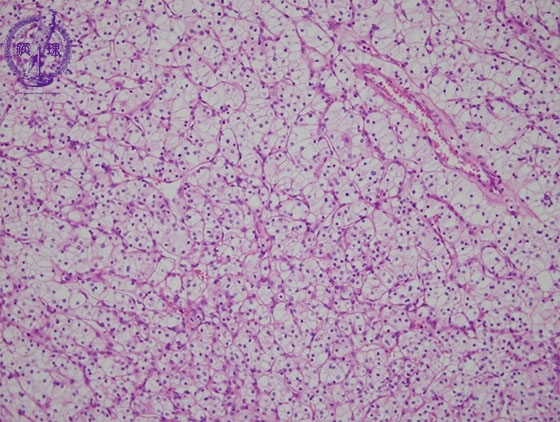

- ★(17)Renal cell carcinoma

Microscopic findings ( HE, middle power view): Renal cell carcinoma (clear cell carcinoma). The tumor cells are arranged in an alveolar manner associated with a fine sinusoid-like capillary network (red dotted lines).